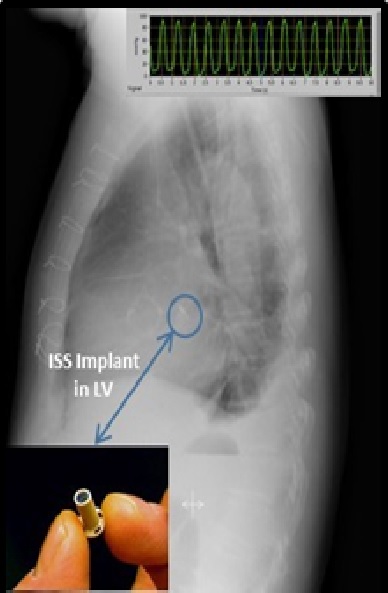

در ماه ژوئیه 2013 برای نخستین بار سیستم‌های حسی مجتمع در بدن چند بیمار قلبی در اروپا (روی بطن چپ و دهلیز چپ قلب) کار گذاشته شد تا اثرات آن را مطالعه کنند. این بیماران به راحتی با این سیستم‌ها زندگی کردند و از قابلیت‌های جالب این دستگاه برای نظارت خانه، نظارت از راه دور به صورت آنلاین و دسترسی به اینترنت بی‌سیم برای دسترسی به پایگاه داده اطلاعات پزشکی لذت بردند. این ایمپلنت‌های هوشمند مینیاتوری نخستین نوع ایمپلنت‌هایی هستند که در سمت چپ قلب در یک مطالعه بالینی نصب شدند.

این سیستم با نام TitanTM IHM و با عنوان کامل سیستم نظارت همودینامیک بی‌سیم قابل کاشت بدون باتری برای اندازه‌گیری و ثبت همودینامیک قلب و عروق، از جمله ریتم، ضربان قلب، تغییرات ضربان قلب، بالا رفتن فشار و نوسانات فشار خون در هر دو وضعیت حاد و مزمن کاربرد دارد. این ایمپلنت تنها یک بار در بدن بیمار جاسازی می‌شود و پس از آن می‌توان با استفاده از یک فرستنده و گیرنده رادیویی از بیرون بدن، دستگاه را به کار انداخت و نتایج اندازه گیری‌های آن را ثبت کرد.

نحوه قرارگیری ایمپلنت در قلب

سیستم تایتان با استفاده از انرژی فرکانس رادیوئی به صورت بی‌سیم هم انرژی مورد نیاز ایمپلنت را تامین می‌کند و هم علائم حیاتی قلب را اندازه می‌گیرد. این سیستم شامل سه بخش است:

ایمپلنت تله‌متری (حسگر) که یک حسگر فشار قابل کاشت بسیار ریز است که نیاز به هیچ منبع انرژی، باتری یا سیم ندارد

واحد نظارت که متشکل از قطعات الکترونیک، آنتن و رابط کاربری است برای نظارت بر بیمار در خانه و بیمارستان

پایگاه داده‌ای که تمام اطلاعات در آن ذخیره می‌شود

هم‌اکنون روی مانیتورهای همودینامیک بی‌سیم و حسگرهای مایع پیشرفته کار می‌کنم که می‌تواند تصویر آنها را در عکس زیر ببینید.